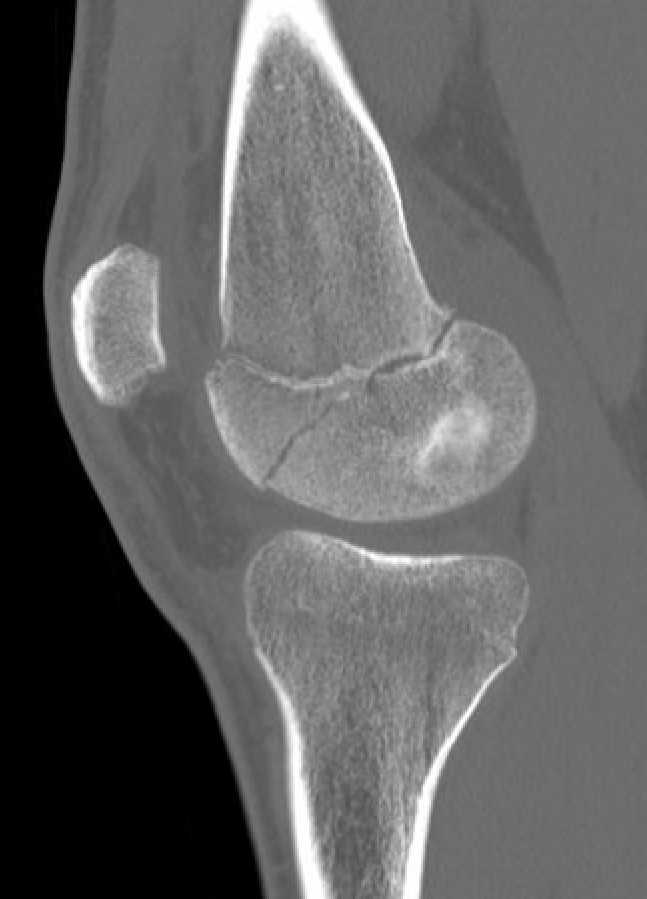

Partial growth arrest / angular deformity

SH2Dis femurDis femur

Management

CT / MRI - assess percentage of bony bridge

Bony bridge < 50%

- excision and fat graft

- manage angular deformity with 8 plates / osteotomy

Bony bridge > 50%

- hemi-epiphysiodesis

- may need later correction of LLD and angular deformity